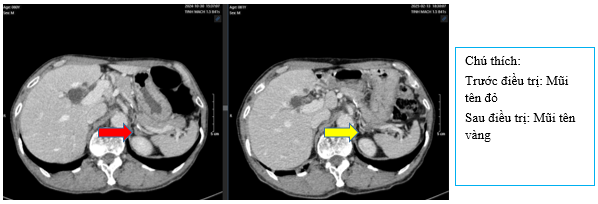

- Chụp CT bụng tháng 10/2024 (trước điều trị)

Hình 3:

Hình ảnh dày cành trong tuyến thượng thận trái 11mm (mũi tên đỏ), gan có vài nang, lớn nhất đường kính 30mm (mũi tên vàng)

- Chụp CT bụng sau điều trị:

Hình 9: So sánh phim chụp CT bụng trước điều trị nốt tuyến thượng thận ~11mm (mũi tên đỏ) đã giảm nhẹ kích thước sau điều trị còn ~9mm (mũi tên vàng)